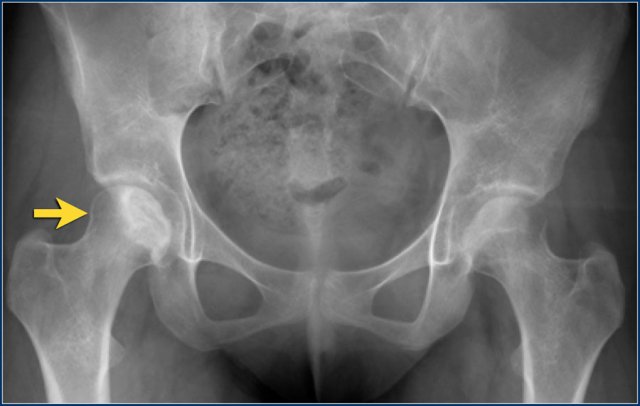

The x-ray is of a 15-year old with acute lymphatic leukemia who was treated with steroids.

The images alone cannot differentiate from Perthes disease, but based on the clinical information, this is secondary avascular necrosis.